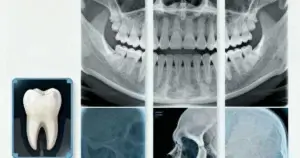

Radiografías dentales: Tipos y seguridad

La salud dental es clave para nuestro bienestar. En la odontología moderna, las radiografías dentales son esenciales. Ayudan a diagnosticar y tratar